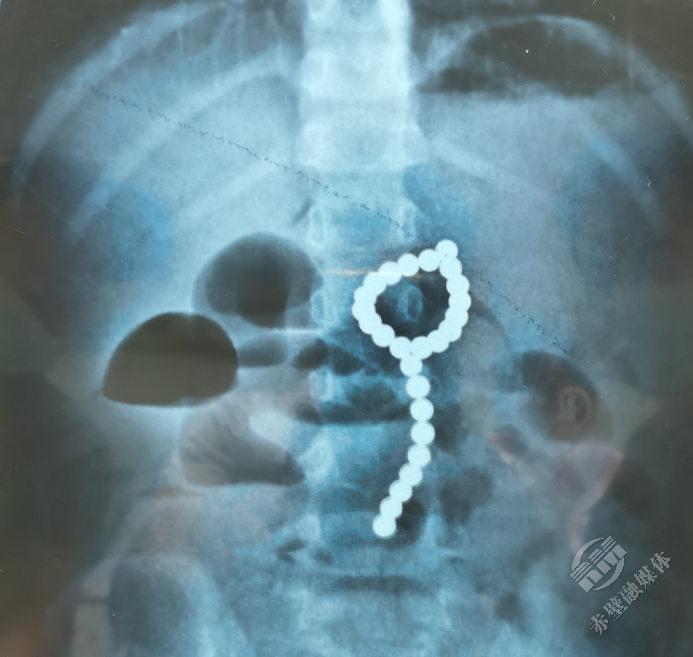

拍片显示女孩腹部有一串珠子。武汉儿童医供图

4岁女孩莎莎(化名)平时健康活泼,家住鄂南地区。8月11日晚上,她吃晚饭后总说“肚子痛”,疼得厉害时大汗淋漓,还吐了几次。家长担心是吃坏了肚子,就莎莎带到当地医院就诊。拍片发现,莎莎腹部有异常高密度阴影,看形状像是一颗一颗的小珠子,一数有26颗。在父母的追问下,莎莎才说她吞了“彩色的小珠珠”,推测应该是家里的玩具磁力珠。

在全麻胃镜检查中,医生发现莎莎胃里有大量成串的磁力珠,部分堆积在胃幽门口,成串“骑跨”在胃角上。拨动磁力珠发现,有一颗磁力珠深陷在胃壁中,考虑穿孔可能很大,经内镜中心远程会诊,并和普外科讨论后,决定直接转外科手术。

外科医生在莎莎胃内共找到了26颗磁力珠并顺利取出,和当地检查数目一致。担心影像片有重叠导致有“漏网之鱼”,医生术中再给莎莎拍胸腹部X片,好在没有新的发现。之后,医生继续探查肠道共发现六处穿孔,逐一精心修补。